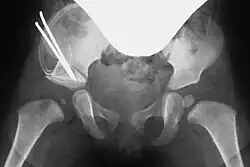

In both techniques, a suitably shaped bone wedge is inserted into the resulting gap under X-ray guidance. If needed, the wedge can be fixed with an osteosynthesis wire (Kirschner wire). The procedure typically takes 45 to 60 minutes for an experienced surgeon.[3][11]

Post-surgery, a pelvic spica cast (modified Fettweiss cast) or abduction orthosis is applied to keep the femoral head centered in the acetabulum during healing. Anesthesia is discontinued afterward.[7]

The postoperative immobilizing cast is typically worn for six weeks, with X-ray checks after one and three weeks. A cast change, often requiring additional anesthesia, is performed after six weeks. The cast is worn for three months, followed by a splint. Regular follow-up examinations are essential, with longer recovery periods for older children.[7]